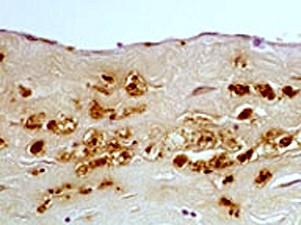

问题 动脉粥样硬化最具有特征性的病变是 ( )

选项 A、血管内膜表面破溃形成血栓及机化 B、动脉壁的弹力层和肌层破坏后血管破裂引起出血 C、局限于动脉内膜的脂质条纹病变 D、纤维斑块发生出血、坏死、溃疡的复合病变 E、纤维斑块病变引起管腔狭窄

答案 E